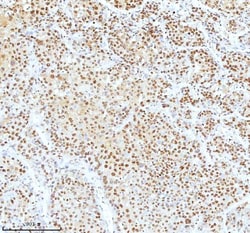

Reconstitute with 0.2 mL of distilled water to yield a concentration of 500 μg/mL. Positive Control - WB: human LNCAP whole cell, human Hela whole cell, human 293T whole cell, human HepG2 whole cell, human Jurkat whole cell, human K562 whole cell, human A549 whole cell, human A431 whole cell. IHC: human bladder cancer tissue, human bladder cancer tissue, human colon adenocarcinoma tissue, human colon adenocarcinoma tissue, human glioblastoma tissue, human glioblastoma tissue, human liver cancer tissue, human liver cancer tissue, human lung adenocarcinoma tissue, human lung adenocarcinoma tissue, human pancreas ductal adenocarcinoma tissue, human pancreas ductal adenocarcinoma tissue, human testicular seminoma tissue, human testicular seminoma tissue. ICC/IF: U2OS cell. Flow: A431 cell. Store at -20°C for one year from date of receipt. After reconstitution, at 4°C for one month. It can also be aliquotted and stored frozen at -20°C for six months. Avoid repeated freeze-thaw cycles.